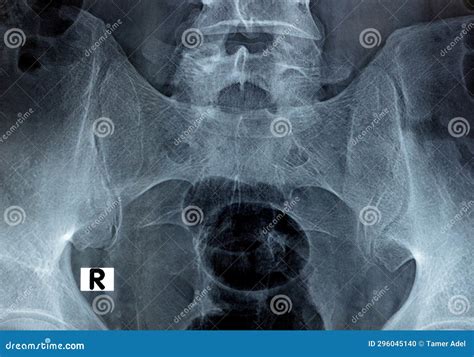

Si Joint Xray

Persistent lower back, buttock, or hip pain can be debilitating, often leaving individuals searching for answers regarding the structural integrity of their pelvis. One of the primary diagnostic tools utilized by healthcare professionals to investigate these symptoms is the Si Joint Xray. The sacroiliac (SI) joints are located at the base of the spine where the sacrum connects to the ilium (the large pelvic bone). While these joints allow for minimal movement, they act as critical shock absorbers for the upper body. When inflammation, degeneration, or trauma affects these joints, diagnostic imaging becomes essential for an accurate diagnosis and subsequent treatment plan.

Once the Si Joint Xray is completed, the images are sent to a radiologist. The radiologist carefully examines the films for specific "red flags" or markers of pathology. The findings are compiled into a report that is sent back to your ordering physician.

Key findings in a report often include:

• Joint Space Width: A narrowing of the joint space often indicates wear and tear or degenerative joint disease.

• Sclerosis: This refers to an increase in bone density around the joint, which is a common response to chronic stress or inflammation.

• Erosions: Small "nibbles" in the bone surface, which are highly suggestive of inflammatory arthritis.

• Ankylosis: The fusion of the joint, where the space between the bones has disappeared entirely.

It is vital to understand that radiological findings must be correlated with clinical symptoms. Some individuals may show minor degenerative changes on an Si Joint Xray but experience no pain, while others may have significant pain despite "normal-looking" imaging results. Your doctor will weigh your physical pain, range of motion tests, and history against these images to determine the next steps.